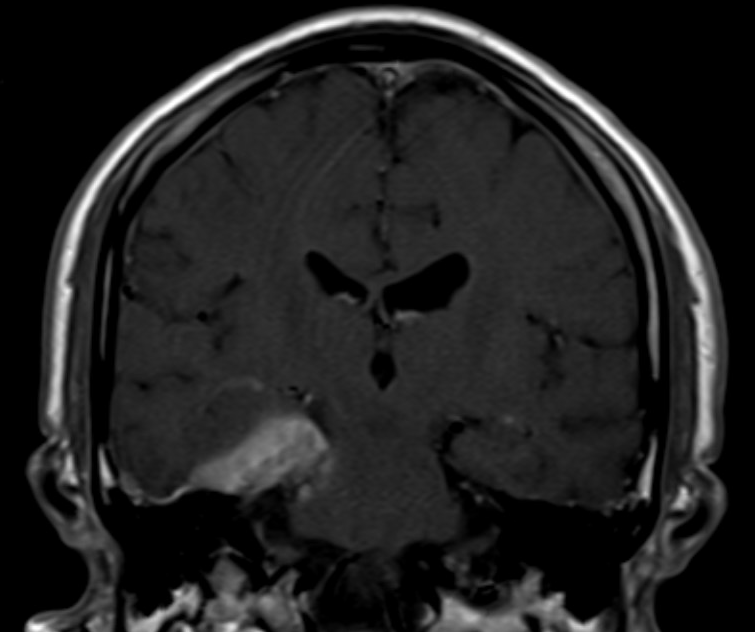

- This is a case of neurosarcodosis with pachymeningial involvement of the right tentorium. There was suspected involvement of the trochlear nerve (CN IV) in this region with resulting atrophy of the right superior oblique muscle.

- Neurosarcoidosis has a variable appearance on MR imaging, with nodular leptomeningeal disease and cranial nerve enhancement (especially facial nerve) being common imaging findings

- Additional possible findings include coating of the hypothalamus and optic chiasm, thickening of the pituitary infundibulum, and enhancing intraaxial masses